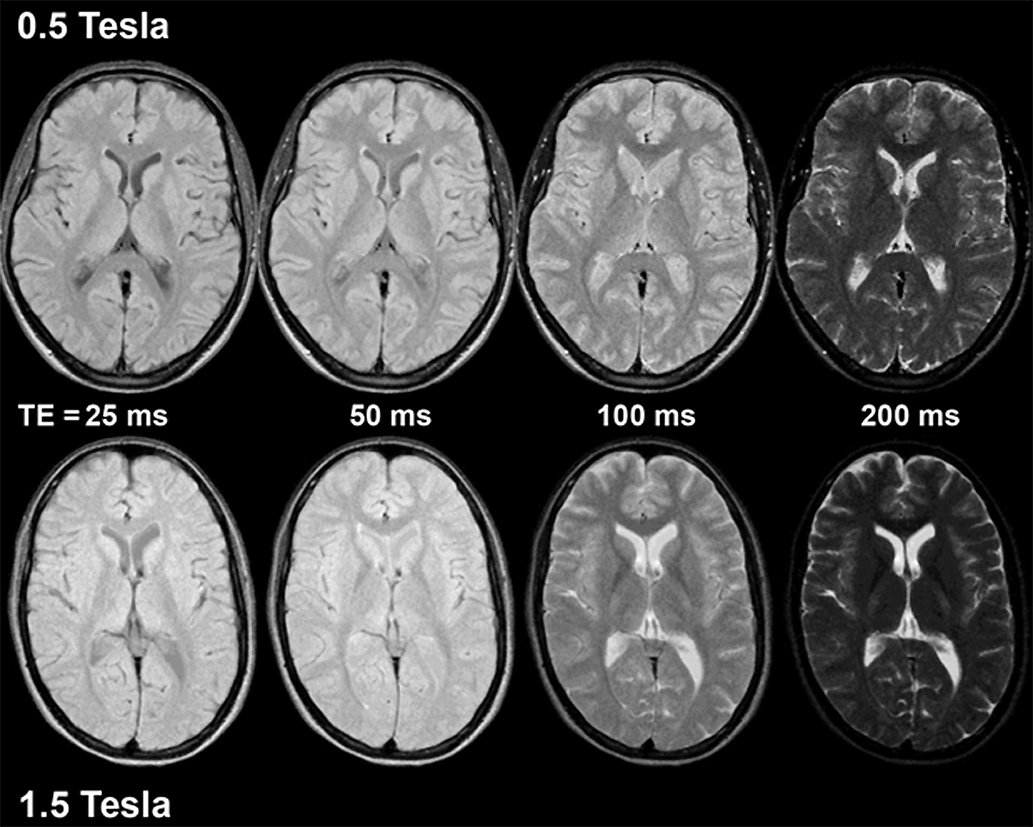

When comparing MR images acquired at different field strength, it is important to keep in mind that T1 grows with field strength. This increase is the reason why ima­ges taken with the same pulse pa­ra­me­ters, but at different fields, change their con­trast ap­pea­rance. Thus, they can­not be directly compared with each other, as the com­pa­ri­son of Figure 10-16 shows.

Figura 10-16:

Image series on top at 0.5 Tesla, on bottom at 1.5 Tesla; TR = 2000 ms. Contrast changes and differs bet­ween the two field strengths using the same imaging pa­rameters.

Animation: The image series on the left side was taken at 0.5 Tesla, the one to the right at 1.5 Tesla at a re­pe­ti­tion time TR = 2000 ms. Compare how contrast changes and differs between the two field strengths using the same imaging parameters.